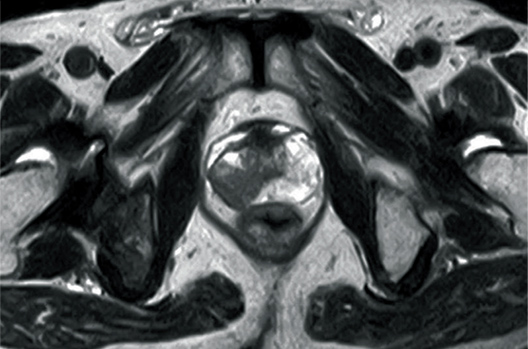

T2WI